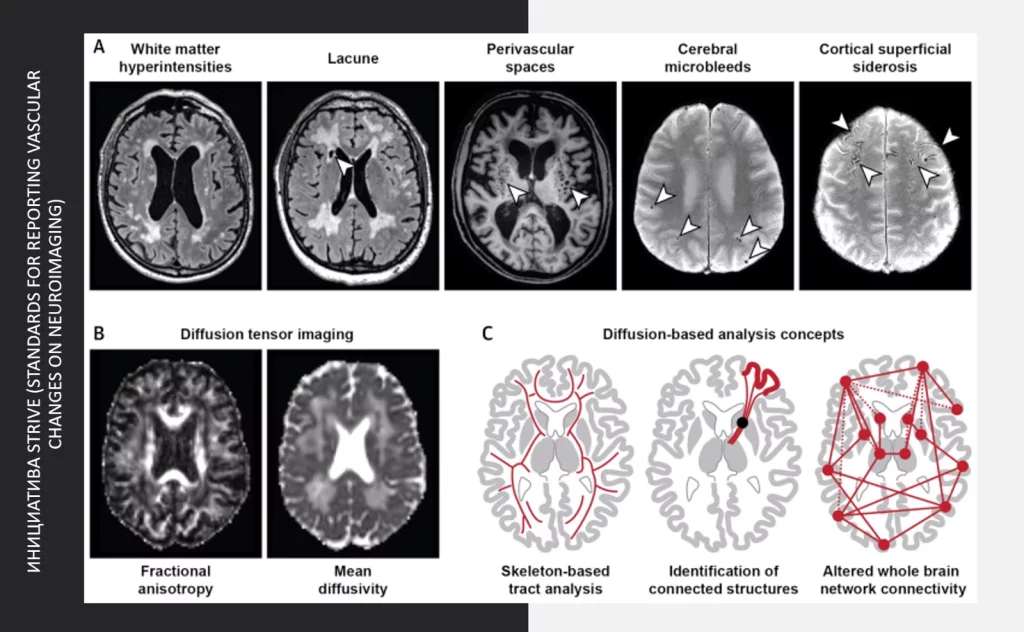

Есть очень четкие критерии по нейровизуализационным показателям, которые можно обнаружить у пациентов с сосудистыми, либо с нейродегенеративными нарушениями.

Выше представлены протоколы STRIVE, с которыми многие знакомы.

Они описывают фенотипы сосудистых нарушений, которые можно визуализировать по данным магнитно-резонансной томографии и, соответственно, решать вопрос, будут ли эти процессы протекать в разряде сосудистых патологий или нейродегенерации.